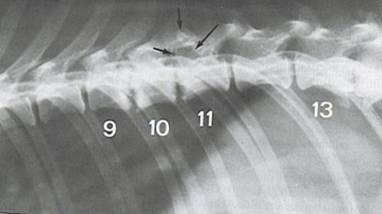

Spondylosis, Spondylarthrosis

Diese Abnutzungs- und Alterserkrankung tritt v.a. im Bereich der Brust- und Lendenwirbelsäule auf. Auffallend dass diese Krankheiten bei gewissen Rassen und Zuchtlinien gehäuft auftritt und bereits in jungen Jahren zum tragen kommt. Degenerative Prozesse mit brückenförmigen Auswüchsen an der unteren Seite der Wirbelkörper sind erkennbar. Auch eine Verknöcherung der Bänder der kleinen Wirbelgelenke ist möglich. Die Spondylose wird meist bei grossen Rassen als Zufallsbefund festgestellt, da sie im Anfangsstadium keinen oder nur einen mässigen Einfluss auf die körperliche Leistungsfähigkeit hat.  Im fortgeschrittenen Stadium sind Steifheit der Wirbelsäule, v.a. im Lendenbereich und gespannter Gang feststellbar, die Tiere jaulen auf, wenn sie berührt werden. Sie können sich nur mühsam erheben, vermeiden das Treppensteigen und schnelle Bewegungen und schränken ihre Spaziergänge ein. Im Endstadium hängt der Schwanz schlaff herunter, die Tiere können nicht mehr die typische Stellung für Harn und Kotabsatz einnehmen, es treten Lähmungen und Muskelatrophie ein.

Auch hier gilt, je früher die Behandlung einsetzt, desto vorteilhafter für das Tier, es ist nämlich durchaus möglich mit verschiedenen biologischen Dauertherapien den Verknöcherungsvorgang aufzuhalten und in den besten Fällen sogar rückgängig zu machen. Im Zweifelsfall bringt eine Röntgenuntersuchung die klare Antwort. Bei prädestinierten Rassen oder Zuchtlinien empfiehlt es sich eine entsprechende Präventionsbehandlung anzustreben.